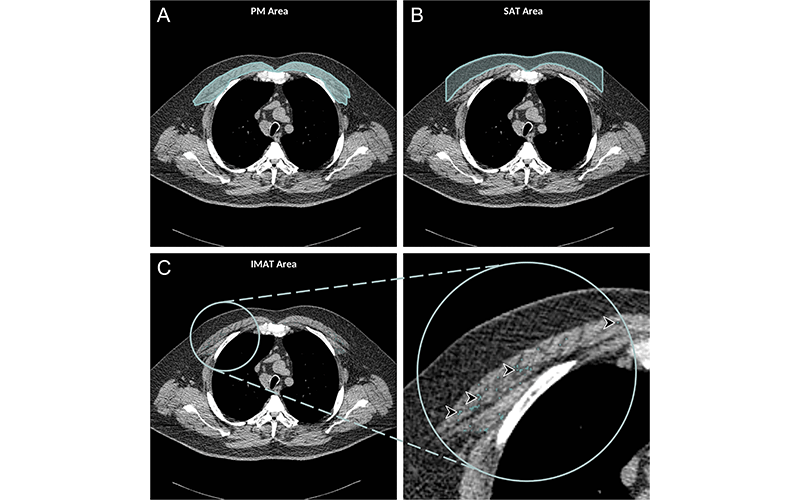

A greater amount of intermuscular fat was associated with higher mortality rates. Existing research has linked higher levels of intermuscular fat with diabetes and insulin resistance.

Higher subcutaneous adipose tissue, in contrast, was linked to lower risks of all-cause mortality.

The authors convincingly showed fat in the muscle was much more predictive of bad outcomes than a simple distribution of subcutaneous fat.